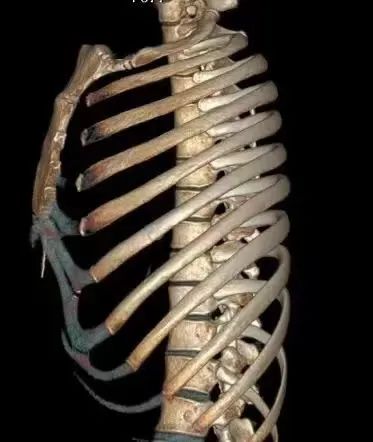

完善肋骨CT三维重建后,清晰提示左侧第6肋骨折。询问得知,杨女士经常出门过度防晒,长期接触不到光照。医生称,发生肋骨骨折的患者通常是有长期或剧烈的咳嗽史,伴随本身的骨质疏松或转移性骨肿瘤等病症。建议杨女士完善检查,明确是否有骨质疏松。